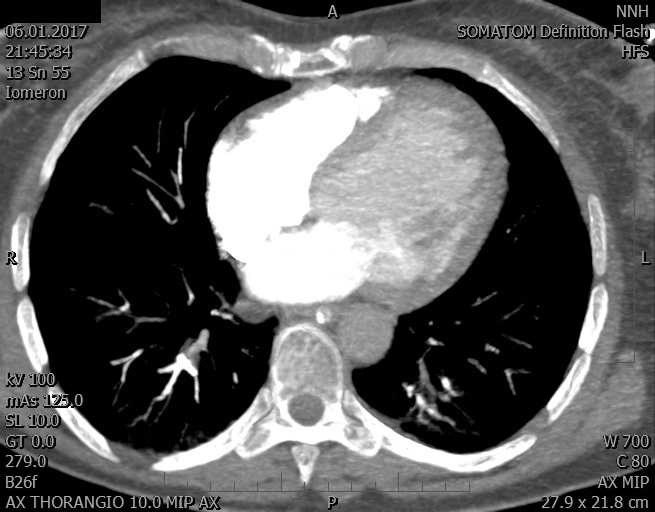

Video 2 - Echokardiograficky byla zjištěna těžká dysfunkce dilatační levé komory s nezvětšenou pravou komorou.Pro nejasnou příčinu zástavy jsme provedli i vyšetření výpočetní tomografií (CT), které vyloučilo plicní embolizaci (série 1 - soubory na konci článku). V den přijetí při přetrvávající oběhové nestabilitě byla nemocná opakovaně defibrilována pro fibrilaci komor se stabilizací rytmu po podání amiodaronu a mesocainu. Dle hemodynamických měření se jednalo o těžký kombinovaný šok. Vstupní laboratorní vyšetření bylo bez větších pozoruhodností. Posléze jsme doplnili anamnézu od příbuzných a zjistili, že pacientka užila do dvou hodin před srdeční zástavou první tabletu amoxicilinu na lehký respirační infekt. Při nevýtěžnosti vstupních vyšetření a nových anamnestických informacích jsme doplnili 14 hodin po kolapsu vyšetření koncentrace tryptázy v séru, která byla extrémně zvýšena (tabulka 2), což nás vedlo k podezření na anafylaxi.